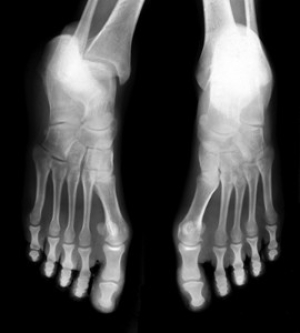

Stress fractures generally occur as a result of an injury that is caused by overusing the foot. A stress fracture is defined as a hairline crack in one of the metatarsal bones in the foot, and can be common among people who participate in running and jumping activities. Pain and discomfort may be felt in the center of the foot, which may also appear swollen. Mild relief may be found when the activity that caused the fracture is stopped, and the affected foot is frequently elevated. A proper diagnosis generally consists of having an X-ray, MRI, or CT scan performed, and is followed by implementing an effective treatment plan. This can consist of resting the foot for several weeks, walking with crutches, or wearing a cast. If you have endured a stress fracture, please consult with a podiatrist who can guide you toward treatment methods that will work for you.

Common symptoms of stress fractures are pain and swelling near the weight bearing area on the injured bone. When initial x-rays are performed, it is possible that the fracture will not show up. However, once the stress on the area continues, the damage will increase, and the fracture will be severe enough to show up on an x-ray. Certain parts of the foot are more likely to develop stress fractures than others. Areas that typically have these fractures are: the metatarsals, the navicular bone, the calcaneus, tibia, and fibula.